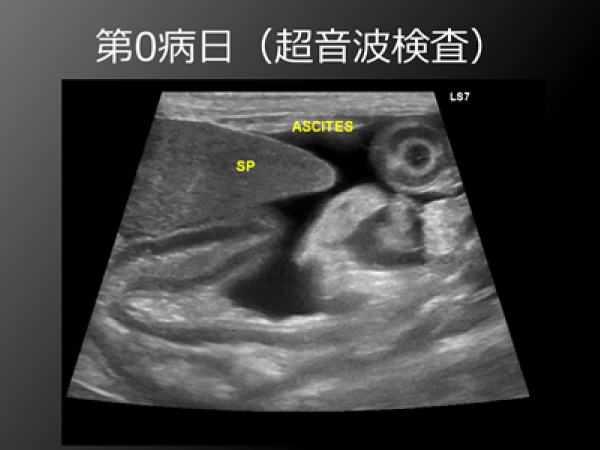

初診時は腹水と黄疸があり、食欲もなく痩せていた。

門脈造影では多発性のシャント血管を認めた。

門脈造影では門脈圧の亢進による多発性のシャント血管(黄色矢印)を認めた。